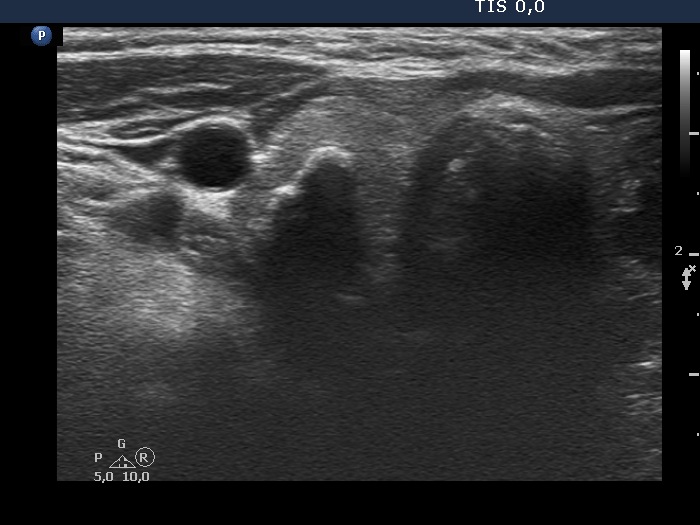

Ultrasonography. The thyroid was echonormal. There was a nodule presenting coarse calcification along its ventral surface. There was a spongiform-type cyst in the left lobe. The nodule has numerous echogenic figures most of them were caused clearly by posterior back wall enhancement.